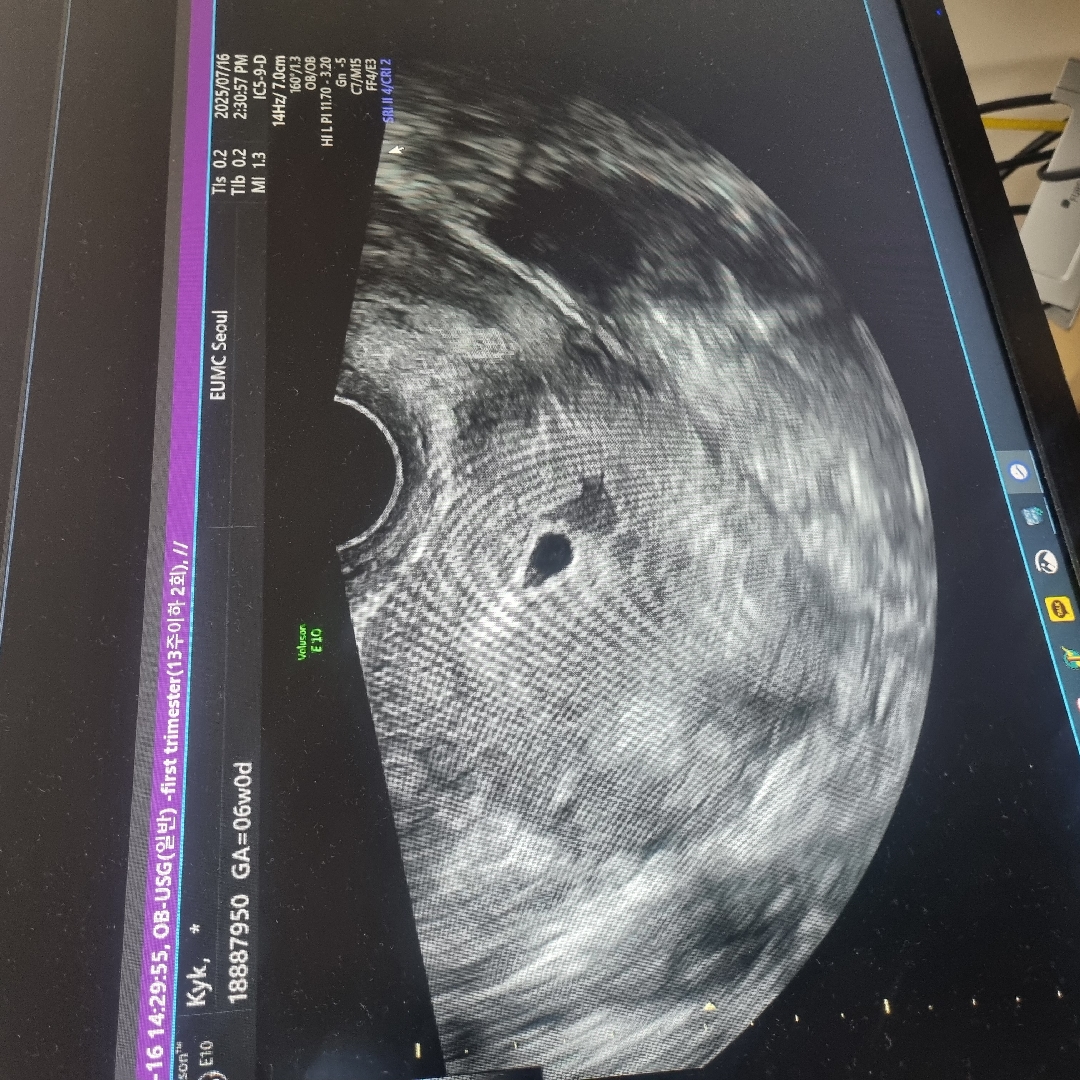

5주1일차 피고임(난황+아기집 확인)

5주1일차 예쁜 난황이랑 아기집 확인했네요 근데 의사쌤이 피고임이 크다고 하시네요ㅠ 피고임은 비교적 흔한 증상이라고 절대 안정만 잘 취하라고 하시는데 피고임이 좀 크셨다가 싸악 사라지신 분들 많으실까요??